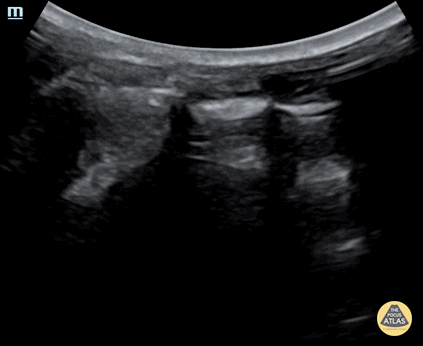

Trauma - Normal Lung Sliding

Normal lung sliding on Efast in a 21-month-old patient. Contributor: Jaron Smith, MD, Phoenix Children's Hospital